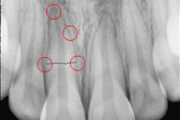

Põhimõtted – Trauma tagajärjel irdunud jäävhammast tasub alati tagasi istutada, kui õnnetuses on hammas ja alveool terveks jäänud. Kui ka hammas hiljem kaotataks, on istutamine tähtis, sest see kergendab implanteerimist ja lükkab edasi hamba asendamist proteesiga. – Mingil juhul ei Loe edasi »